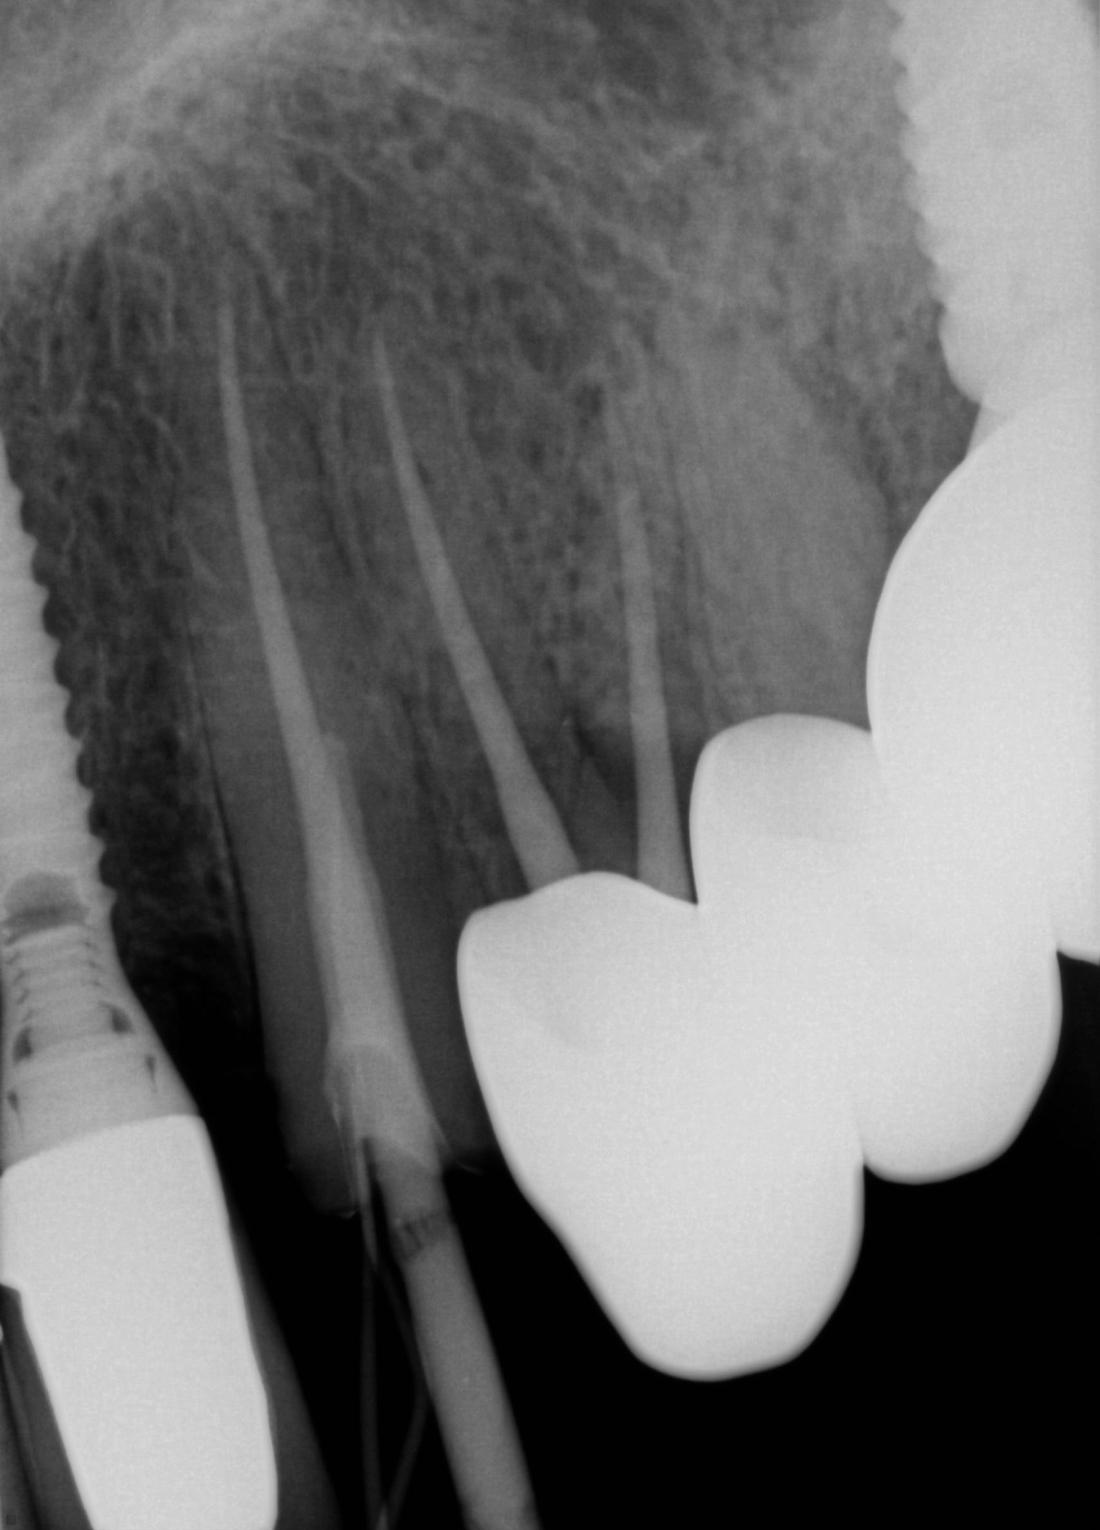

Here is an example of a tooth that had broken off at the gumline.  While people often think that every broken tooth must be pulled, in this case, we were able to do a root canal, followed by a cast post and core, and then cement a crown over the broken tooth.  This photo of the crown was taken seconds after it was cemented.  Root canals, posts, and crowns have been done for a very long time with a very good success rate, so saving teeth is always our first goal whenever possible.  We expect this tooth to have years and years of continued service.